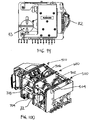

- Fig. 1 is a schematic representation of a hemodialysis system.

- the system 5 includes two flow paths, a blood flow path 10 and a dialysate flow path 20.

- Blood is drawn from a patient.

- a blood flow pump 13 causes the blood to flow around blood flow path 10, drawing the blood from the patient, causing the blood to pass through the dialyzer 14, and returning the blood to the patient.

- the blood may pass through other components, such as a filter and/or an air trap 19, before returning to the patient.

- anticoagulant may be supplied from an anticoagulant supply 11 via an anticoagulant valve 12.

- a dialysate pump 15 draws dialysate from a dialysate supply 16 and causes the dialysate to pass through the dialyzer 14, after which the dialysate can pass through a waste valve 18 and/or return to the dialysate feed via dialysate pump 15.

- a dialysate valve 17 controls the flow of dialysate from the dialysate supply 16.

- the dialyzer is a type of filter having a semi-permeable membrane, and is constructed such that the blood from the blood flow circuit flows through tiny tubes and the dialysate solution circulates around the outside of the tubes. Therapy is achieved by the passing of waste molecules (e.g., urea, creatinine, etc.) and water from the blood through the walls of the tubes and into the dialysate solution. At the end of treatment, the dialysate solution is discarded.